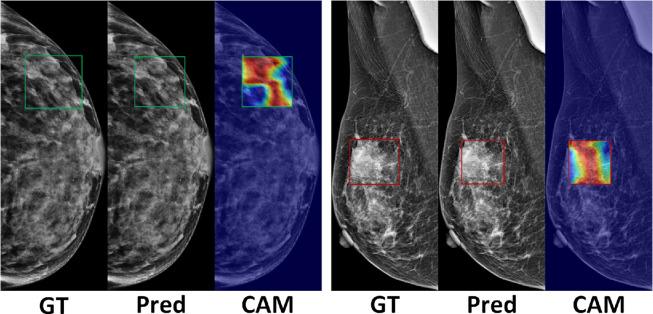

Mammography is the mainstream imaging modality used for breast cancer screening. Identification of microcalcifications associated with malignancy may result in early diagnosis of breast cancer and aid in reducing the morbidity and mortality associated with the disease. Computer-aided diagnosis (CAD) is a promising technique due to its efficiency and accuracy. Here, we demonstrated that an automated deep-learning pipeline for microcalcification detection and classification on mammography can facilitate early diagnosis of breast cancer. This technique can not only provide the classification results of mammography, but also annotate specific calcification regions. A large mammography dataset was collected, including 4,810 mammograms with 6,663 microcalcification lesions based on biopsy results, of which 3,301 were malignant and 3,362 were benign. The system was developed and tested using images from multiple centers. The overall classification accuracy values for discriminating between benign and malignant breasts were 0.8124 for the training set and 0.7237 for the test set. The sensitivity values of malignant breast cancer prediction were 0.8891 for the training set and 0.7778 for the test set. In addition, we collected information regarding pathological sub-type (pathotype) and estrogen receptor (ER) status, and we subsequently explored the effectiveness of deep learning-based pathotype and ER classification. Automated artificial intelligence (AI) systems may assist clinicians in making judgments and improve their efficiency in breast cancer screening, diagnosis, and treatment.